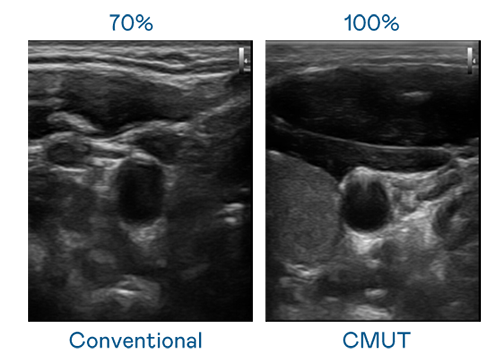

CMUT 技术是一种用电容式微机电元件来产生超音波讯号的技术。与传统 PZT 压电式技术相比,CMUT 频宽增加 30%,更宽频的超音波讯号让影像解析度大幅提升,是实现高影像品质医疗超音波扫描、促进精准医疗发展的关键技术。

大频宽带来超清晰影像

超音波影像的解析度高低,首先取决于探头能发出的讯号频宽。糖果派对 CMUT 可提供高清晰的超音波讯号,提供高频宽、高灵敏度、影像纹理细节更高的超音波影像,协助医护人员缩短影像判读时间及利用精准的医疗影像进行诊断。